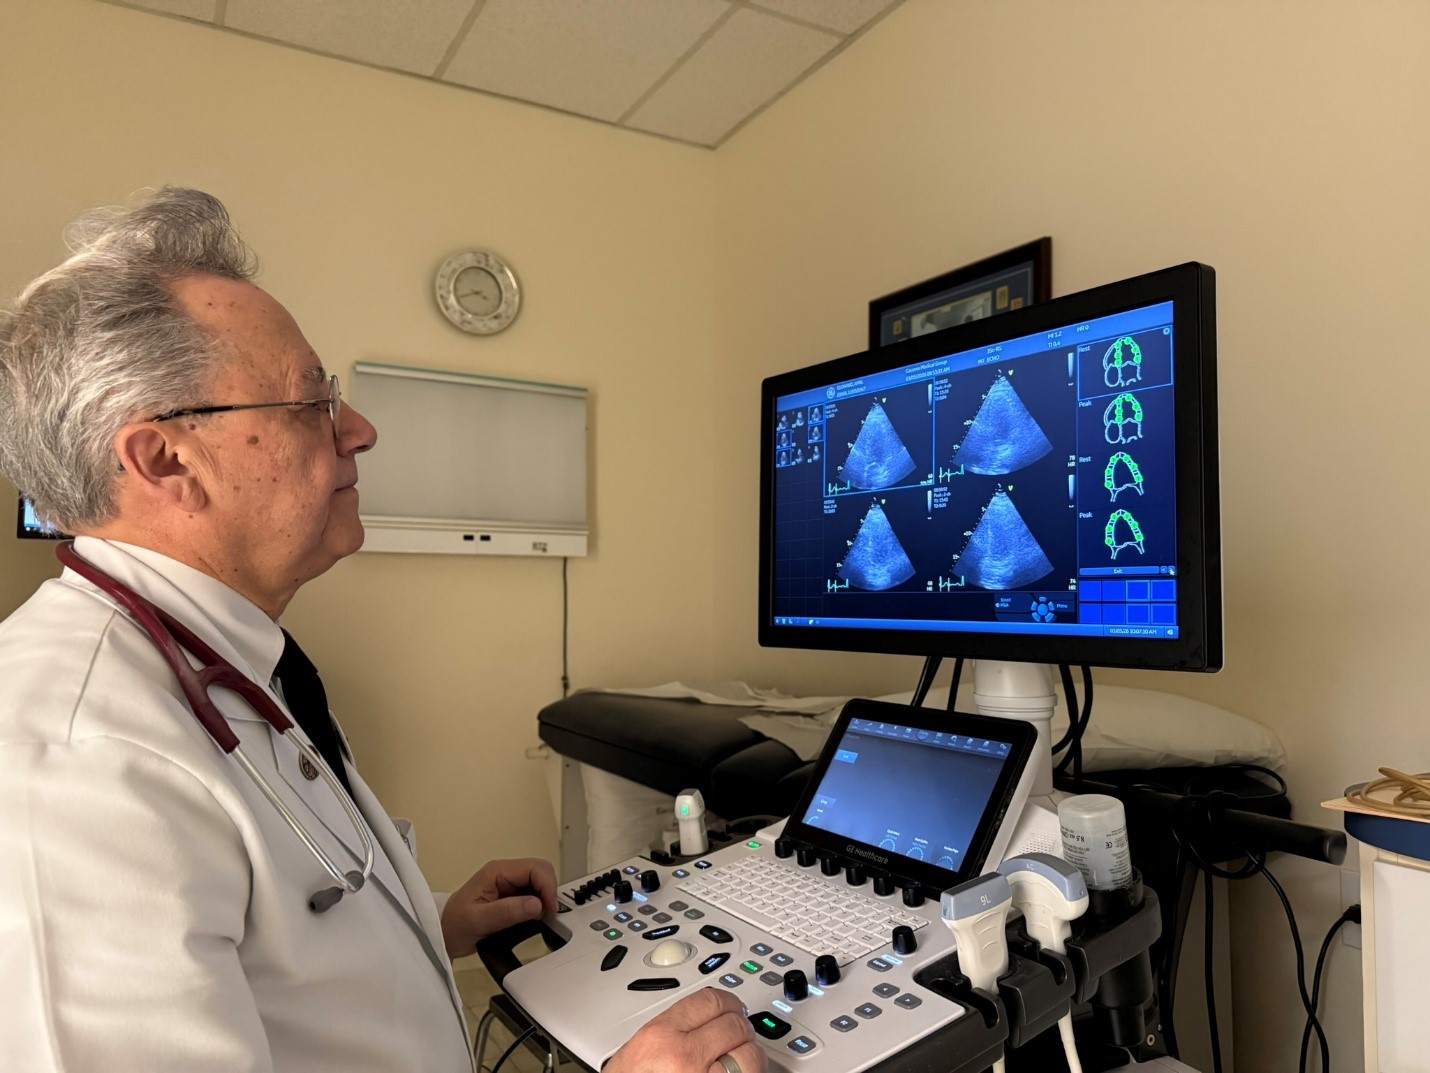

Ultrasound images are obtained before and immediately after exercise.

- A Stress Echocardiogram combines a treadmill stress test with ultrasound imaging of the heart. It allows us to evaluate how well your heart muscle pumps and how effectively blood is supplied to the heart during physical stress.

- Ultrasound images of the heart are taken before exercise and immediately after walking on the treadmill. By comparing these images, we can identify areas of the heart muscle that may not be receiving adequate blood flow from the coronary arteries.

The test typically takes about 20-30 minutes. You will be closely monitored during exercise, and ultrasound images will be obtained before and immediately after the treadmill portion. There is no radiation involved.

Stress echocardiogram images help evaluate blood flow to the heart muscle.